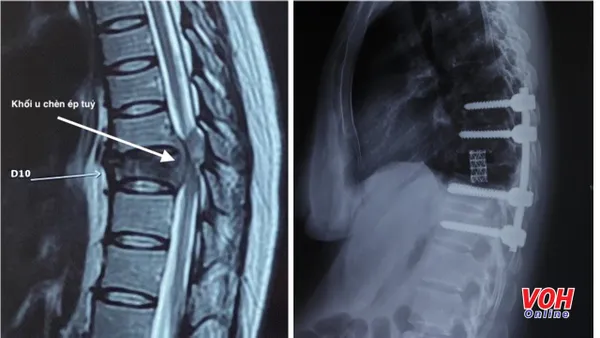

Theo đó, bác sĩ Trí cùng ê kíp phẫu thuật đã tiến hành cố định cột sống bằng bắt vít cuống cung từ đốt sống D8 đến D12 lối sau. Sau đó, khối u được lấy hết đồng thời toàn bộ thân đốt sống D10 được cắt bỏ hoàn toàn để giải phóng thần kinh bị chèn ép.

Cuối cùng lồng kim loại được đặt vào giữa thân sống từ D9-D11 để thay cho thân sống D10 bị hư, như vậy toàn bộ cột sống về lâu dài sẽ vững chắc hơn.